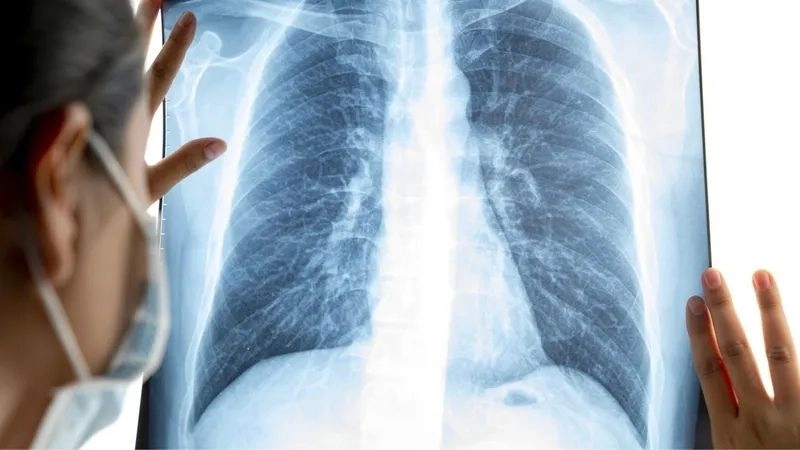

Bệnh bụi phổi (tiếng Anh là Pneumoconiosis) là một trong nhóm bệnh lý phổi kẽ do hít phải một số loại bụi làm tổn thương phổi. Bệnh thường gặp phải ở nơi làm việc nên còn được gọi là bệnh phổi nghề nghiệp.

Đây là tình trạng tích tụ bụi bẩn trong nhiều năm trong phổi và tiến triển thành bệnh. Khi phổi của người bệnh không thể loại bỏ tất cả các hạt bụi này sẽ dẫn đến tình trạng viêm phổi, có thể gây ra các mô sẹo. Bệnh cũng gây tổn thương các mạch máu và túi khí trong phổi, khiến các mô bao quanh túi khí và đường dẫn khí trở nên dày hơn, cứng hơn. Tình trạng này được gọi là bệnh phổi kẽ, lúc này người bệnh có thể gặp các triệu chứng khó thở nặng hơn.

Chụp X-quang ngực và khám sức khỏe định kỳ.